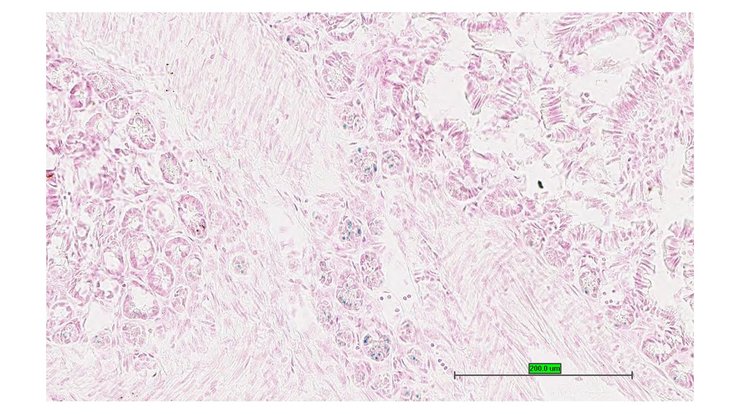

TS28: prostate gland Present UC Davis_1875589

Specimen UC Davis_1875590: postnatal adult; Ghtm1.1(KOMP)Vlcg/Gh+ (more )

Structure Level Pattern Image Note

TS28: prostate gland Present UC Davis_1875590